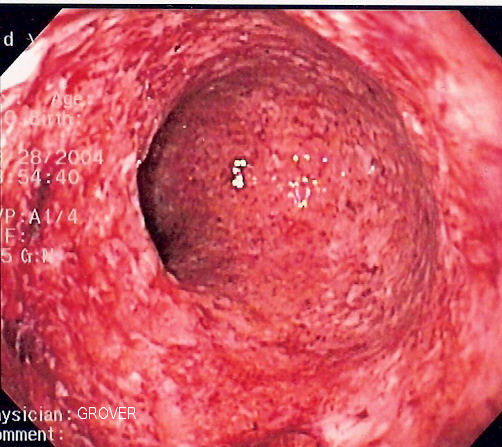

Endoscopic image of severe Crohn's colitis showing diffuse loss of mucosal architecture, friability of mucosa in sigmoid colon and exudate on wall. Photo released into public domain on permission of patient. -- Samir धर्म 07:37, 2 June 2006 (UTC)

| current | 07:37, 2 June 2006 | 502×447 (73 KB) | Samir ( Talk | contribs) | ( Endoscopic image of severe Crohn's colitis showing diffuse loss of mucosal architecture, friability of mucosa in sigmoid colon and exudate on wall. Photo released into public domain on permission) |